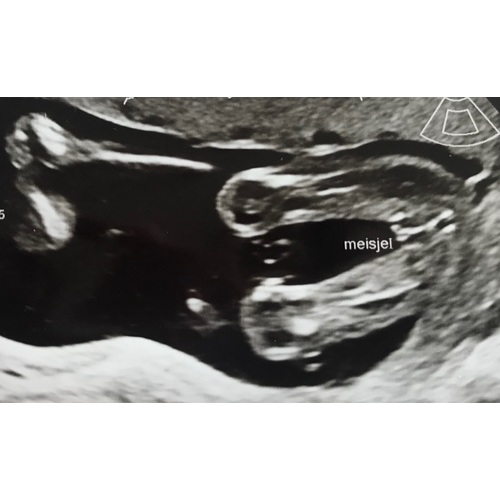

Duidelijk een jongen. Ik krijg een meisje en daarbij zag je duidelijk de hamburger, hier zie je echt balletjes.